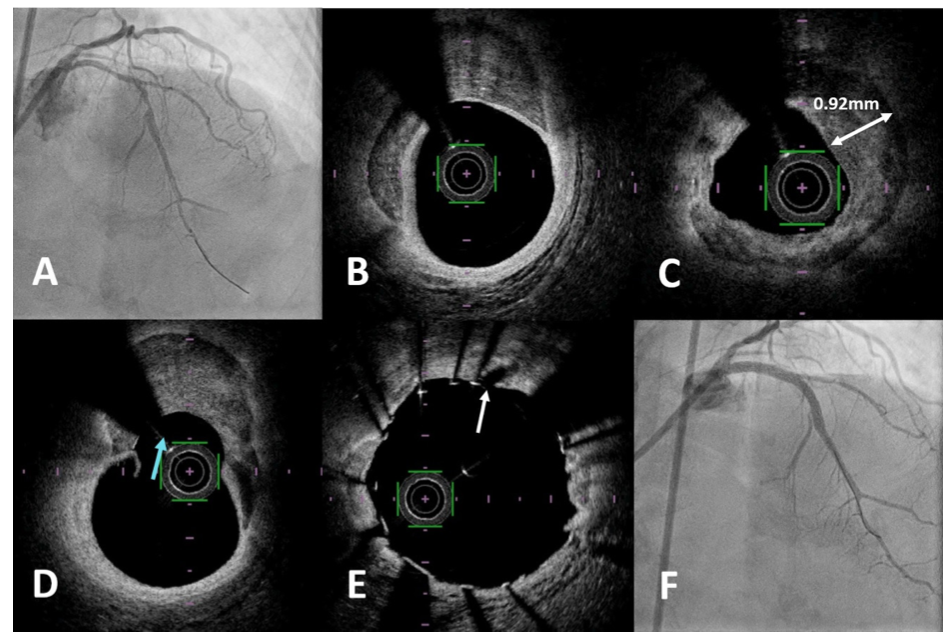

Orbital-tripsy patient #8. A 78-year-old woman with hypertension and type 2 diabetes mellitus underwent an elective coronary angiography following an abnormal computed tomography coronary angiography. The baseline angiogram showed a calcified proximal to mid LAD (Figure 4A). Baseline OFDI was acquired and showed eccentric calcification in the mid LAD (Figure 4B)and concentric calcification in the proximal LAD (Figure 4C), with maximal thickness of 0.92 mm. The workhorse wire was switched out for the ViperWire Advance to perform multiple low- (80,000 rpm) and high-speed (120,000 rpm) OA runs in the calcified segment, followed by another OFDI run to assess the calcium modification. A classic “snowman” appearance was seen in the eccentrically calcified mid LAD, a common finding after OA (Figure 4D). This unique appearance is due to the bidirectional ability of OA to ablate calcification. In the mid LAD, forward OA runs typically bias the crown toward the outer curve (diagonal side) whereas backward OA runs bias toward the inner curve (septal side). In this case, the eccentric calcification was on the inner curve, therefore, preferential ablation in this segment was achieved by predominantly backward OA runs, then advancing the crown beyond the lesion with GlideAssist mode between each run. The concentric calcification in the proximal LAD remained minimally modified by OA, therefore, a 3.0 x 12-mm IVL balloon was chosen to modify this segment. However, predilation with a 2.5 x 15-mm non-compliant balloon was required to deliver the IVL balloon, with post-stent OFDI showing calcium fractures (Figure 4E). Final angiographic result is shown in Figure 4F.

Orbital-tripsy patient #4. A 69-year-old man underwent a staged procedure to a calcified mid to distal LAD after primary PCI to his proximal LAD for an anterior ST-segment-elevation MI (Figure 3A). Past medical history was also significant for hypertension, type 2 diabetes mellitus, and dyslipidemia. The OCT catheter was unable to cross the lesion for baseline assessment, therefore, the workhorse guidewire was switched for a ViperWire Advance for OA using multiple low- (80,000 rpm) and high-speed (120,000 rpm) runs, taking care to start beyond the recently placed proximal LAD stent. OCT then showed a calcium arc of 260°, MLA of 2.25 mm2, and maximum calcium thickness of 0.91 mm at the most calcified segment (Figure 3B). A 2.5 x 12-mm IVL balloon was then used in this segment to further prepare the lesion, with a repeat OCT run showing the MLA increased to 4.94 mm2 and new fractures in the calcium (Figure 3C). Dissections penetrating both intimal and medial layers can be seen post IVL distal to the most calcified segment (Figure 3D). Following stenting and balloon optimization, the final OCT run showed an MSA of 6.36 mm2 (Figure 3E). Final angiographic result is shown in Figure 3F.